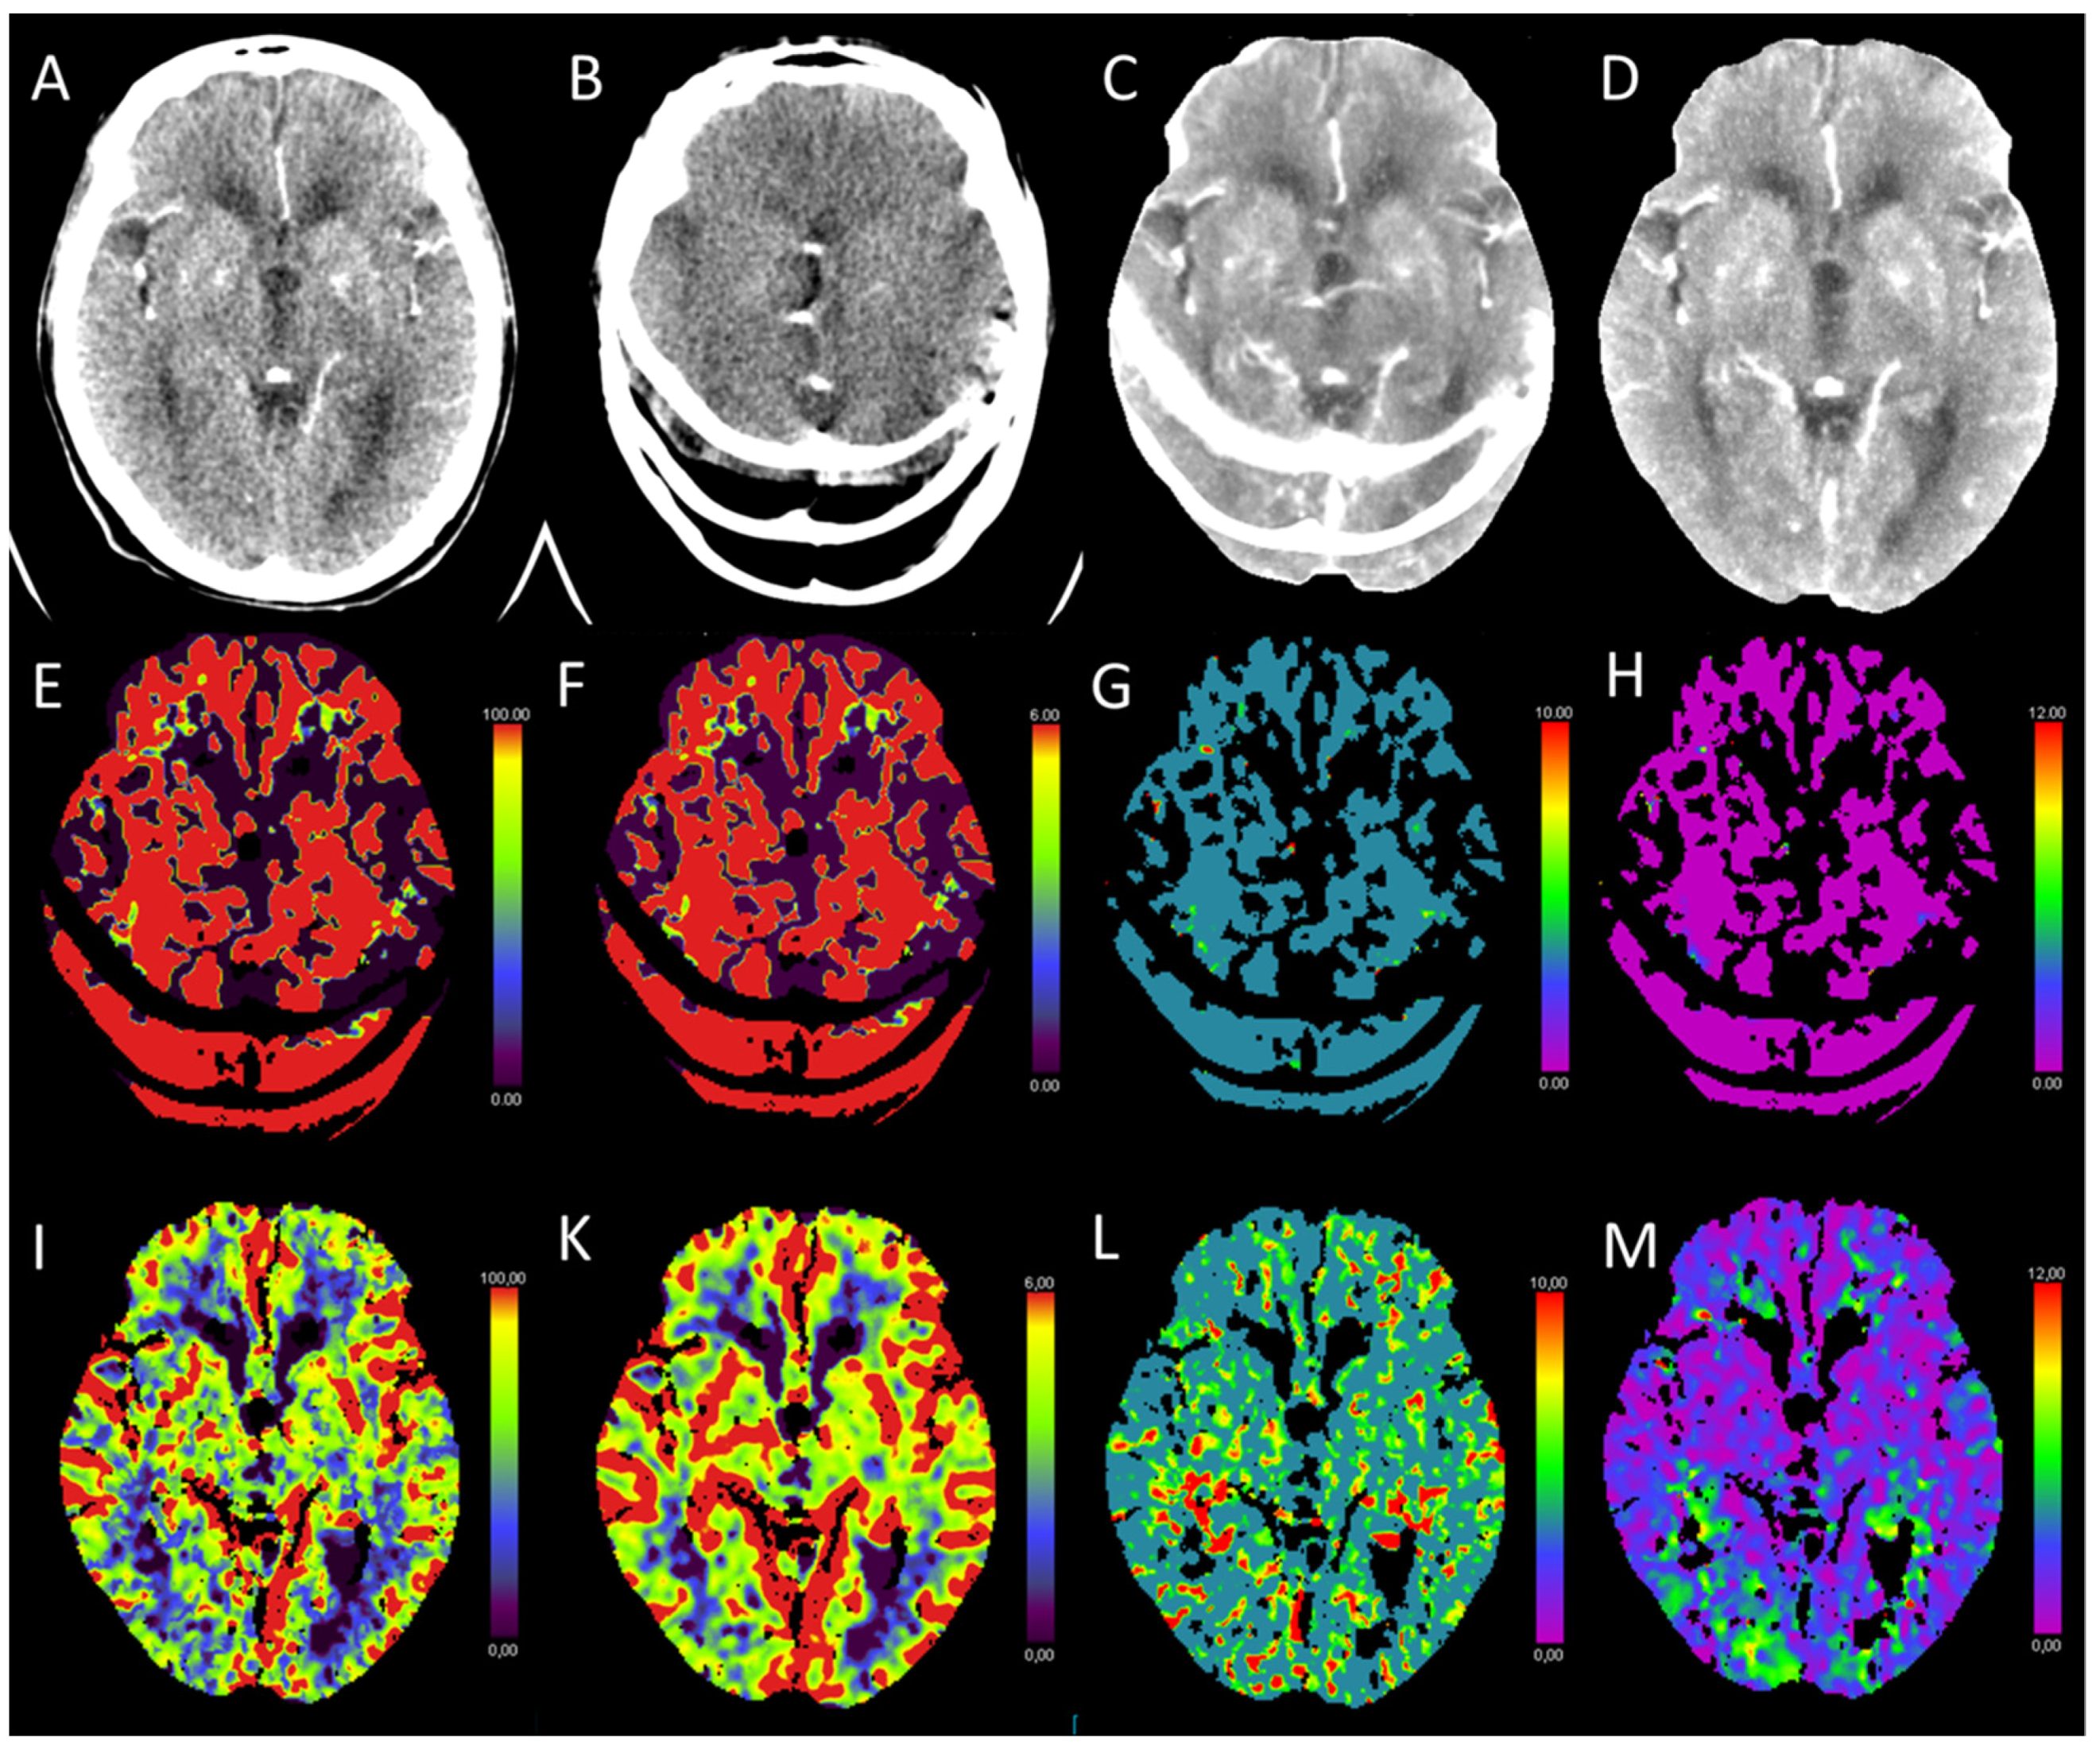

3.10. Postictal Stroke Mimics

- Van Cauwenberge, M.G.A.; Dekeyzer, S.; Nikoubashman, O.; Dafotakis, M.; Wiesmann, M. Can perfusion CT unmask postictal stroke mimics? A case-control study of 133 patients. Neurology 2018, 91, e1918–e1927. [Google Scholar] [CrossRef]

- Hauf, M.; Slotboom, J.; Nirkko, A.; von Bredow, F.; Ozdoba, C.; Wiest, R. Cortical regional hyperperfusion in nonconvulsive status epilepticus measured by dynamic brain perfusion CT. AJNR Am. J. Neuroradiol. 2009, 30, 693–698. [Google Scholar] [CrossRef]